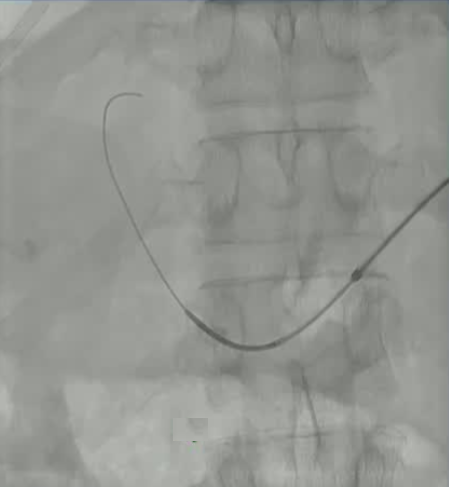

该程序包含以下步骤: 经脾脏入路:在超声引导下,刺穿脾静脉内的一个实质内分支。 在通过脾静脉造影确认了静脉通路后,导管和导丝被推进,以穿过脾静脉并抵达血栓化的门静脉。在门静脉/右门静脉分支处放置圈套器,为TIPS穿刺精准定位。TIPS穿刺圈套器,并穿过圈套器完成TIPS

结果:术后影像学检查显示门静脉和脾静脉的血流情况有所改善,且残留血栓极少。

通过经颈静脉肝内门体分流术(TIPS)治疗慢性门静脉血栓时所涉及的技术复杂性和决策难题,尤其是在标准方法因血栓程度过重而无法实施的情况下更是如此。 采用脾经脏穿刺术治疗门静脉高压症的方法证明能够有效克服这些难题,从而成功实施了经颈静脉肝内门体分流术(TIPS)。 PVR-TIPS 作为一线治疗方案:PVR-TIPS 为慢性门静脉血栓的治疗提供了一种技术上可行的解决方案,克服了标准 TIPS 安装所面临的难题。 持久效果:该干预措施不仅恢复了门静脉的血流,而且在后续随访中还显示出持续的通畅性以及血栓的完全消散。